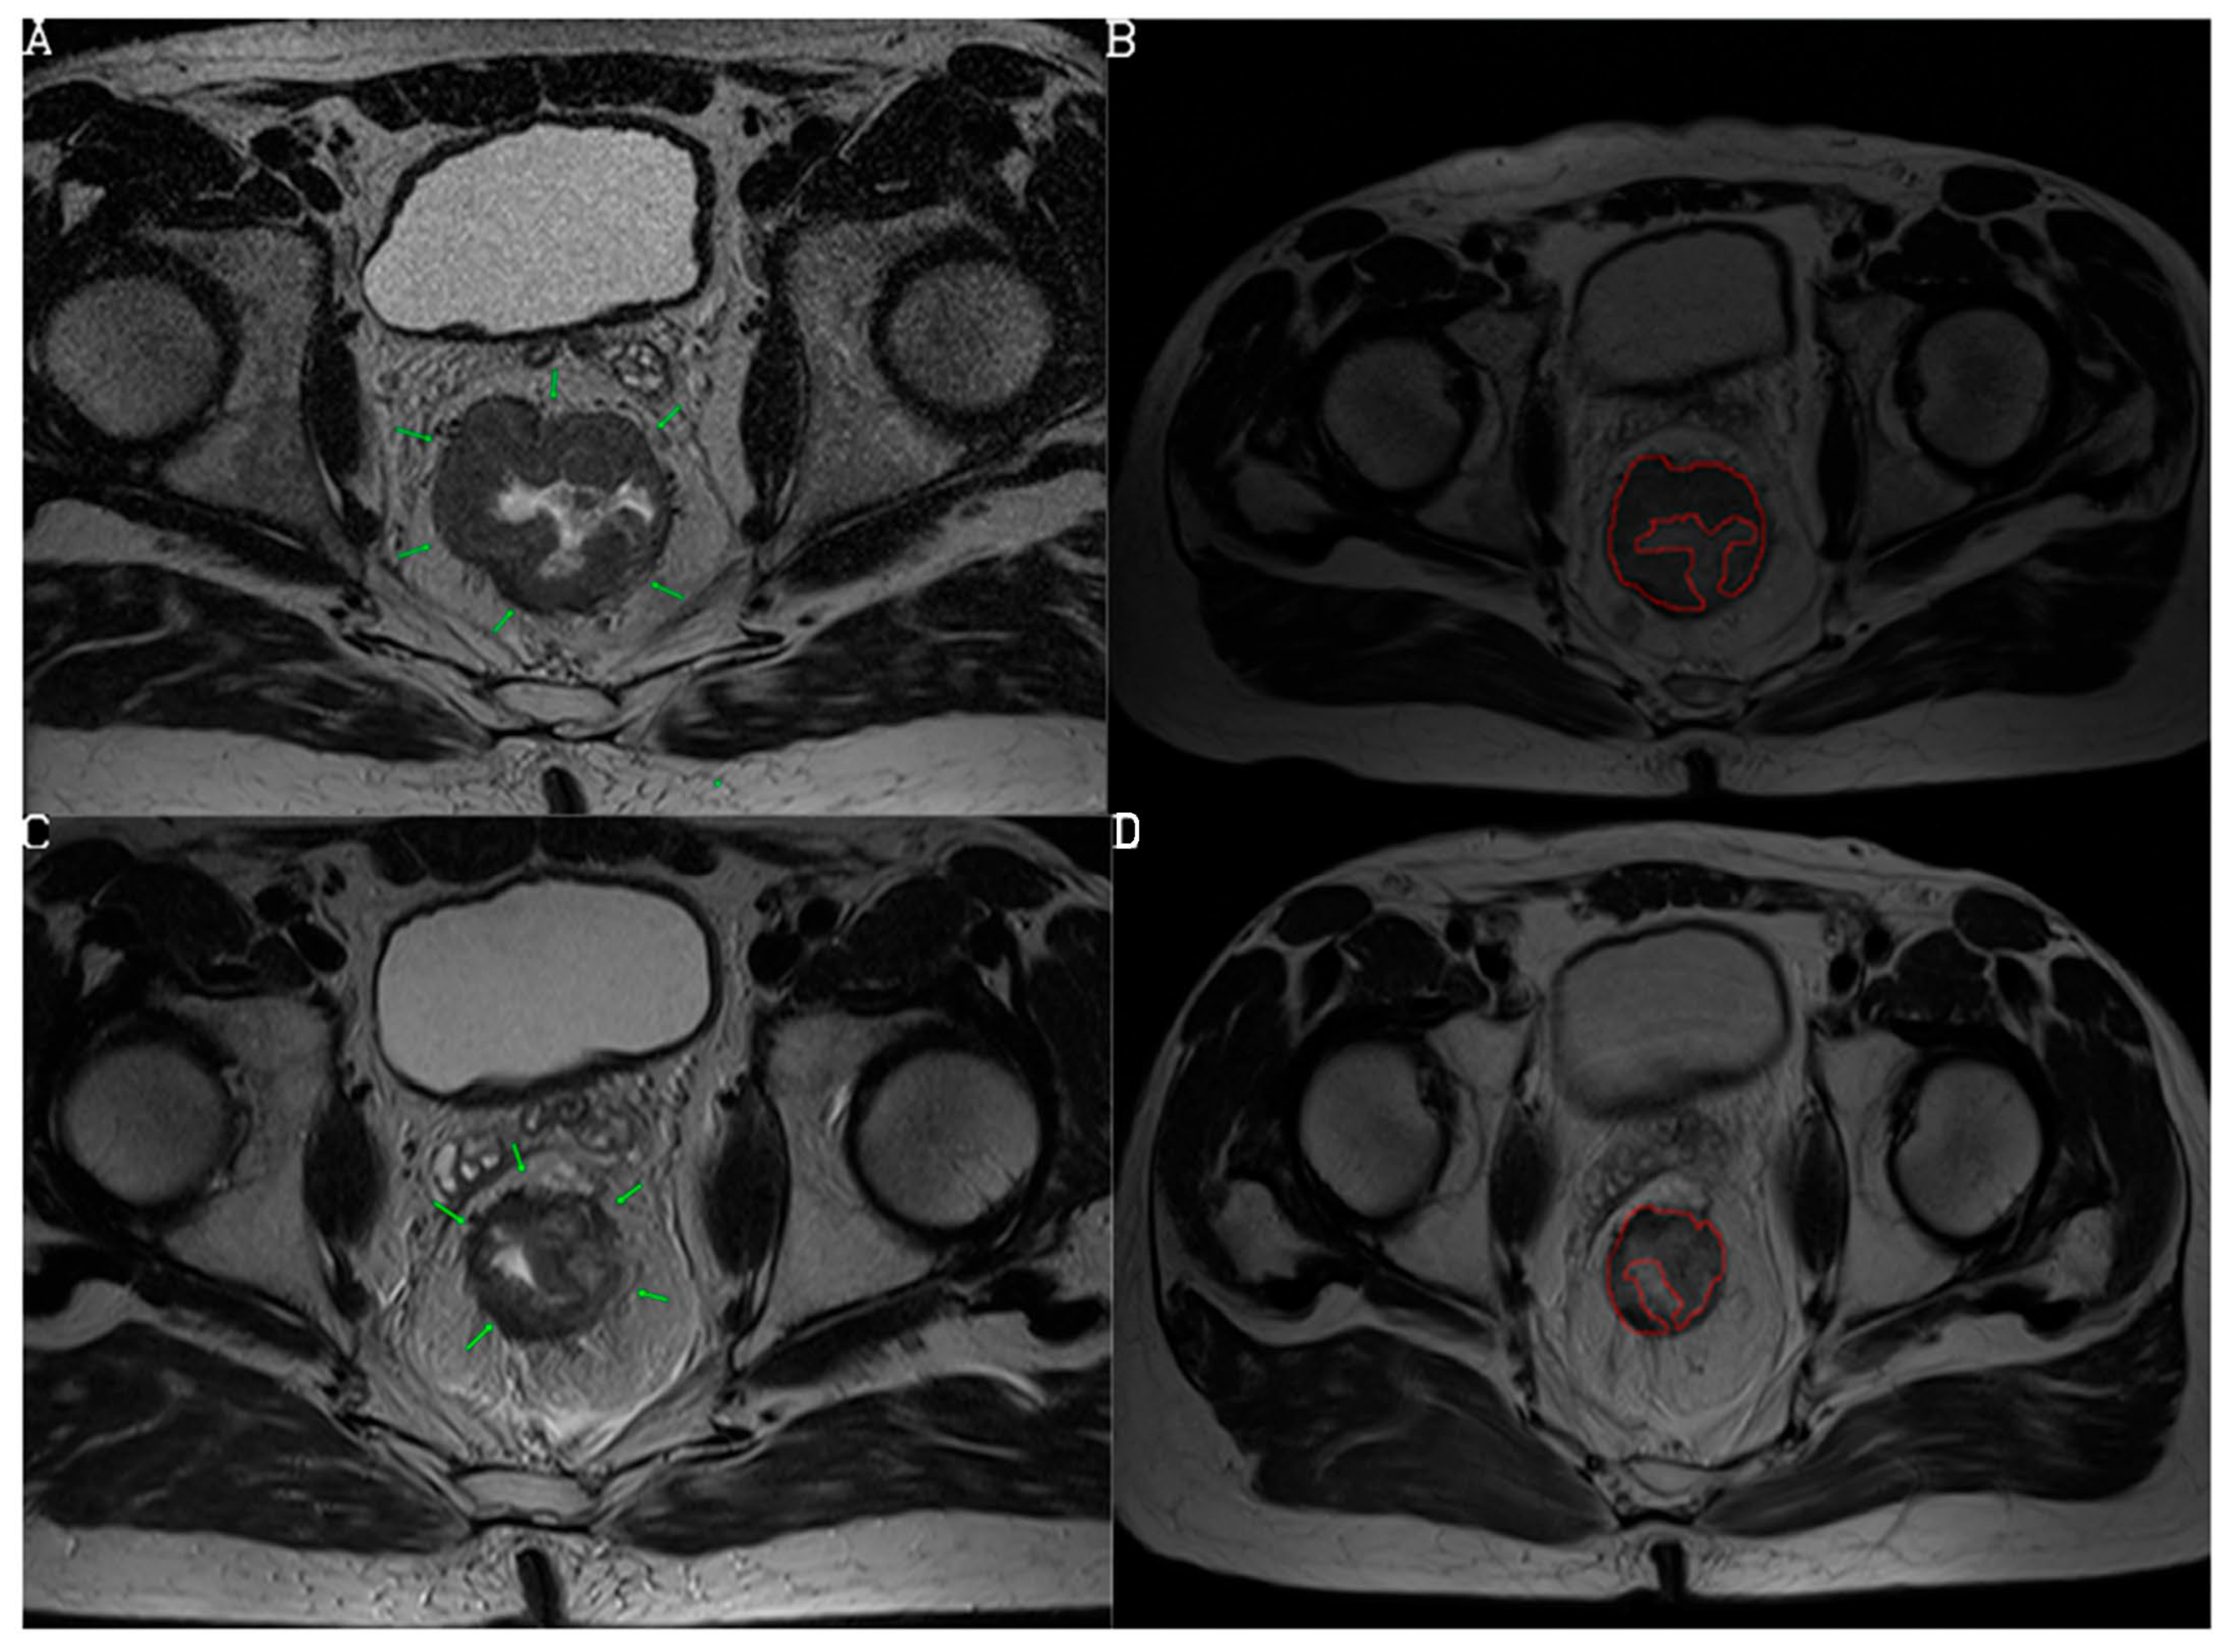

3.2. Diagnostic Performance of mrTRG